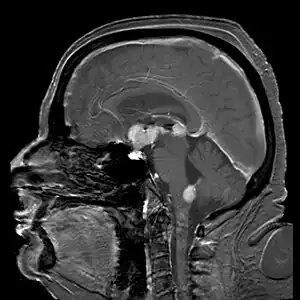

Brain magnetic resonance imaging showing primary central nervous system B-cell non-Hodgkin lymphoma of the sella turcica and hypothalamus, continuing to the tectum (intensely white areas in the middle).